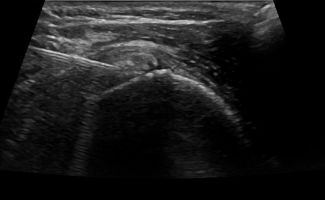

During Barbotage treatment, under local anesthesia and through a minimally invasive approach, calcifications are flushed with saline, and an anti-inflammatory drug is injected into the subacromial-subdeltoid bursa.

Thanks to ultrasound guidance, Barbotage is an effective and entirely safe procedure. The use of ultrasound ensures both the avoidance of vital structures, such as vessels and nerves, and the targeted injection of the therapeutic substance precisely where it is needed at the site of calcifications.